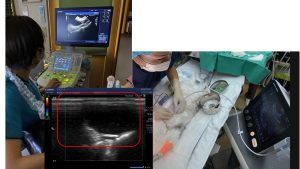

超音波検査で安全に細胞診が実施できます。

細胞診は皮膚がんに限らず、癌の診断と治療方針の決定に極めて重要ですが、

針を癌や体の内部に刺すため、出血などの合併症が心配になります。超音波検査では

針の届くところまで血管の走行や臓器の位置を把握できるため、安全に細胞診を実施すること

が出来ます。